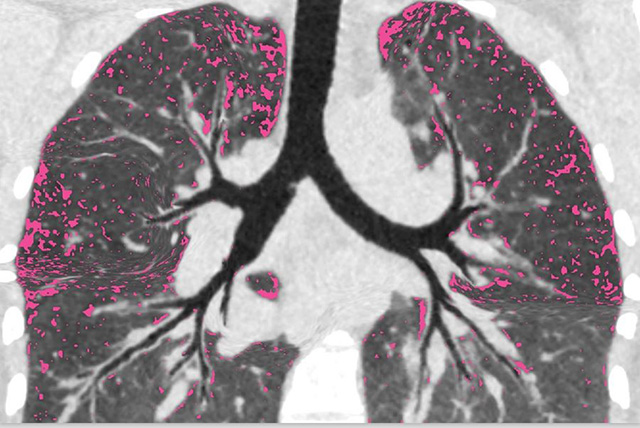

Before the study participants were started on modulators, the researchers went into patients’ lungs with thin cameras called bronchoscopes. They sampled regions that differed in the amount of damage, infection and inflammation. They then revisited the same lung areas a year after treatment to see where infection remained and what lung characteristics were linked to persistent infection.

“What we found was a surprise, and there was good and not so good news,” said Durfey. “The good news was that, when infections cleared, lung inflammation almost completely resolved. Thus, future lung damage could be lessened in people who clear.”

Durfey continued: “However, people who remained infected had infection and inflammation everywhere we looked, including lung areas with very little damage.”

These findings suggest damage might not be the main cause of infection persistence and raise concern that lung function in people with bacterial infection could continue to deteriorate.